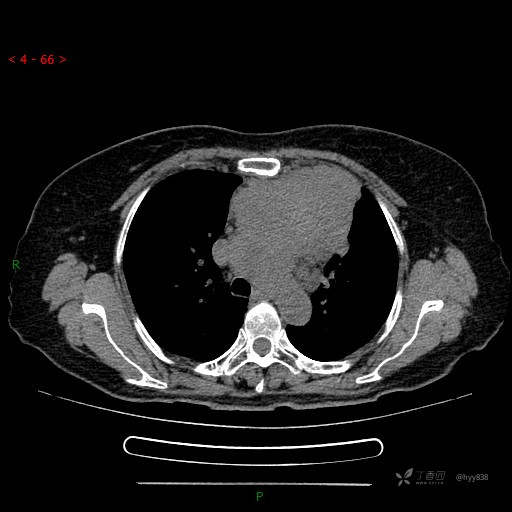

不同于其它肿瘤,针尖“坚硬泥沙样”的感觉,我并给出了病理诊断---结果公布~

简要病史:患者诉3月余前患新冠肺炎,出现持续性胸闷,活动后可缓解,无胸前区压榨感,无畏寒发热不适,无胸痛咯血、呼吸困难,无恶心、呕吐,无腹痛、腹胀、腹泻等不适,未予以重视,未行特殊处理。患者胸闷持续存在,为进一步诊治,3天前于本院查胸部CT提示前纵膈团块状软组织密度影,肿瘤性病变可能,心包积液,左上肺磨玻璃结节,右下肺增殖灶可能建议进一步检查。门诊以“前纵膈占位” 收入我科。 患者本次起病来精神、食欲、睡眠尚可,大小便正常,体力、体重无明显变化。

临床诊断:纵隔占位

穿刺